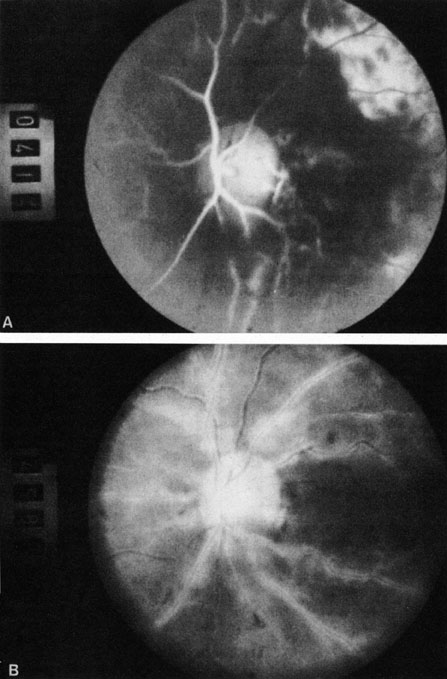

Fig. 1. A: Acute central retinal artery obstruction with a cherry-red spot. B and C: Intravenous fluorescein angiography. There is a delay of dye appearance in the central retinal artery, and when it does appear, it does not fill the arteries completely. D: Ocular coherence tomography (OCT) at the time of occlusion showing the increase in retinal thickness and reflectivity of the inner layers of the retina. E: Seven months later there is significant optic atrophy(G), and the OCT (F) shown now has marked thinning of the retina.

With obstruction, virtually all eyes have narrowing and irregularity in the arteries and there is frequently an irregularity in the caliber of the retinal veins.2,4,6,7 Segmentation (boxcarring) of the blood column frequently develops; this segmentation is particularly noticeable in the veins and can be seen as a to-and-fro movement of the blood elements.3,4 Retinal hemorrhages, however, are not characteristic of central retinal artery obstruction.7

With time, the retinal opacity diminishes, generally leaving an optic nerve that is atrophic (Fig. 1). Frequently, thinned retinal arteries and veins also remain.7,8 No foveolar light reflex is evident, and a finely pigmented appearance of the macula is typical.7 In some cases, arterial collaterals develop at the optic disc.9–11 Rarely, anatomoses that exist between the central retinal artery and the ciliary arteries become visible as preretinal loops (Nettleship collaterals) after an occlusion at the edge of the disc.12,13,378In approximately 20% of patients, an embolus is evident somewhere in the arterial system.14 Emboli are discussed later.

Intravenous fluorescein angiography is useful in showing the details of the abnormal circulation of a central retinal artery obstruction (Fig. 1). The principal abnormality is the delay in the appearance of the dye in the central retinal artery and its branches.2 Rather than the central retinal artery and its branches filling rapidly, considerable time may elapse before the entire arterial system is filled.15 The filling of the retinal arteries is often abnormal, with the fluorescein partially filling an artery (a dye front) or hugging the vessel wall, as in normal venous filling.15

Segmentation of the blood column is often well defined on fluorescein angiography.15 Venous filling is usually slowed and occasionally the dye does not progress beyond laminar flow during the study.14 In approximately 10% of eyes that have central retinal artery obstruction, there are abnormal choroidal filling defects, reflecting posterior circulation obstruction. These defects can occur even in patients who appear to have a typical central retinal artery obstruction.14 Leakage of dye from the vessel walls is not normally seen except at the site where an embolus lodges within a retinal artery.16 With time, the flow within the artery and its branches is reestablished and the appearance of the intravenous fluorescein angiogram may return to normal.